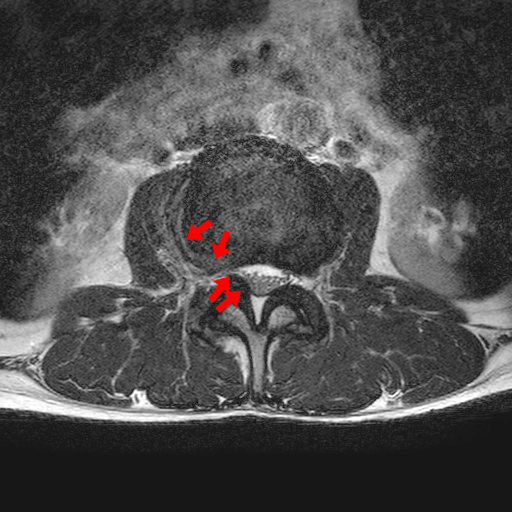

下記は私の腰のMRI画像です。

クリニックにデータが届く日に受診した結果は腰椎の椎間板ヘルニアでした。

同じ体勢でいると右足のみ軽い痺れも出てきていて力が入りにくい感覚があり、

実際力は入るのですが、脱力感というか明らかな違和感があります。

ヘルニアといってもいろいろな状態があるので一概にどうとか言えないみたいですが

「めちゃくちゃ重度というわけではない」と言われました。

でもそれって軽度ではないということですよね…

整形外科に詳しい先生で、ブロック注射も打ててリハビリ施設もあるのに大きな病院に行かないといけないのはここでは対応できないということですよね…